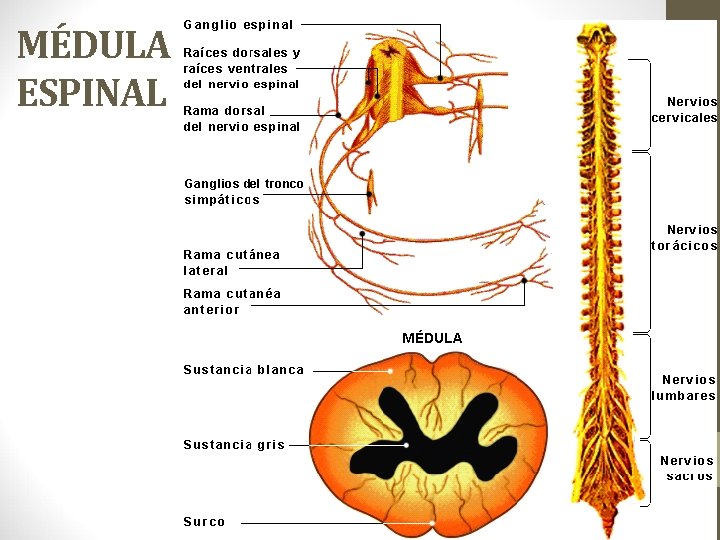

MÉDULA ESPINAL

Cumple una Función conductora (sustancia blanca) y una Función elaboradora de reflejos (sustancia gris)